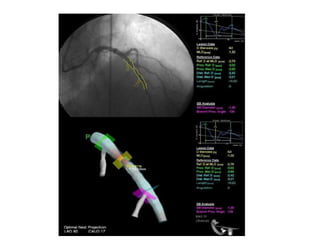

Quantitative Coronary Angiogram

• 2 Dimensional & 3 Dimensional.

• Earlier manually done by calipers later done through

computers.

• Invented by Greg Brown in University of Washington

30 yrs back

• Good quality angiograms at least two orthogonal views

required to avoid

foreshortening, vessel overlapping, irregular margins.

3 D imaging utilizes standard 2 D images 30` apart and

reconstructs